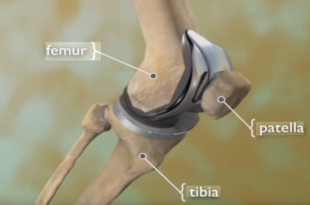

Read More »Best Total Knee Replacement Surgeon in Mumbai – Expert Knee Replacement Treatment

Knee pain is life altering; even normal activities such as walking, climbing stairs or standing for prolonged periods becomes nearly impossible. For individuals with advanced knee arthritis or joint destruction, undergoing a knee replacement procedure can greatly increase mobility and improve their quality of life. Dr. Kunal Patel is one …